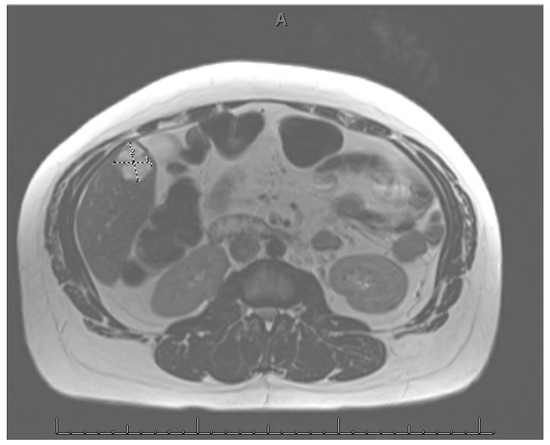

Pregnancy (HP), defined as the coexistence of intrauterine and ectopic gestations, is a rare condition, especially in spontaneous conception, but it is a life-threatening obstetric emergency when rupture occurs, with a reported maternal mortality rate of 0.03%. Diagnosis is often delayed because confirmation of an intrauterine pregnancy can mask clinical signs of a concurrent ectopic gestation. Early recognition and prompt surgical intervention are therefore critical to maternal safety and preservation of intrauterine viability. This case highlights the diagnostic challenges and successful management of a spontaneous ruptured heterotopic pregnancy. Case presentation: A 34-year-old Middle Eastern woman, gravida 4, with a spontaneous conception, presented with sudden severe lower abdominal pain and signs of acute hemoperitoneum (hypotension, tachycardia, and marked peritoneal signs). Transvaginal ultrasound demonstrated a viable intrauterine pregnancy at 9 weeks 4 days gestation, together with a ruptured left tubal ectopic pregnancy of similar gestational age. The patient underwent urgent laparoscopic left salpingectomy with evacuation of approximately 1200 mL of intraperitoneal blood and clots. Postoperatively, she developed significant anemia (hemoglobin drop from 11.2 g/dL on admission to 6.5 g/dL) requiring transfusion of four units of packed red blood cells. Serial ultrasonographic follow-up confirmed ongoing viability of the intrauterine pregnancy, which ultimately resulted in a live birth at term. Progressive resolution of the postoperative pelvic hematoma was also noted. Conclusions: Ruptured heterotopic pregnancy remains a diagnostic and therapeutic challenge. This case, along with a synthesis of the contemporary literature, demonstrates that a high clinical index of suspicion, timely ultrasound diagnosis, and immediate minimally invasive surgical management are paramount. Furthermore, rigorous postoperative monitoring and resuscitation, including targeted transfusion, are essential to achieve maternal stabilization while allowing continuation of a viable intrauterine pregnancy, with reported live birth rates exceeding 70% following timely intervention. Full article